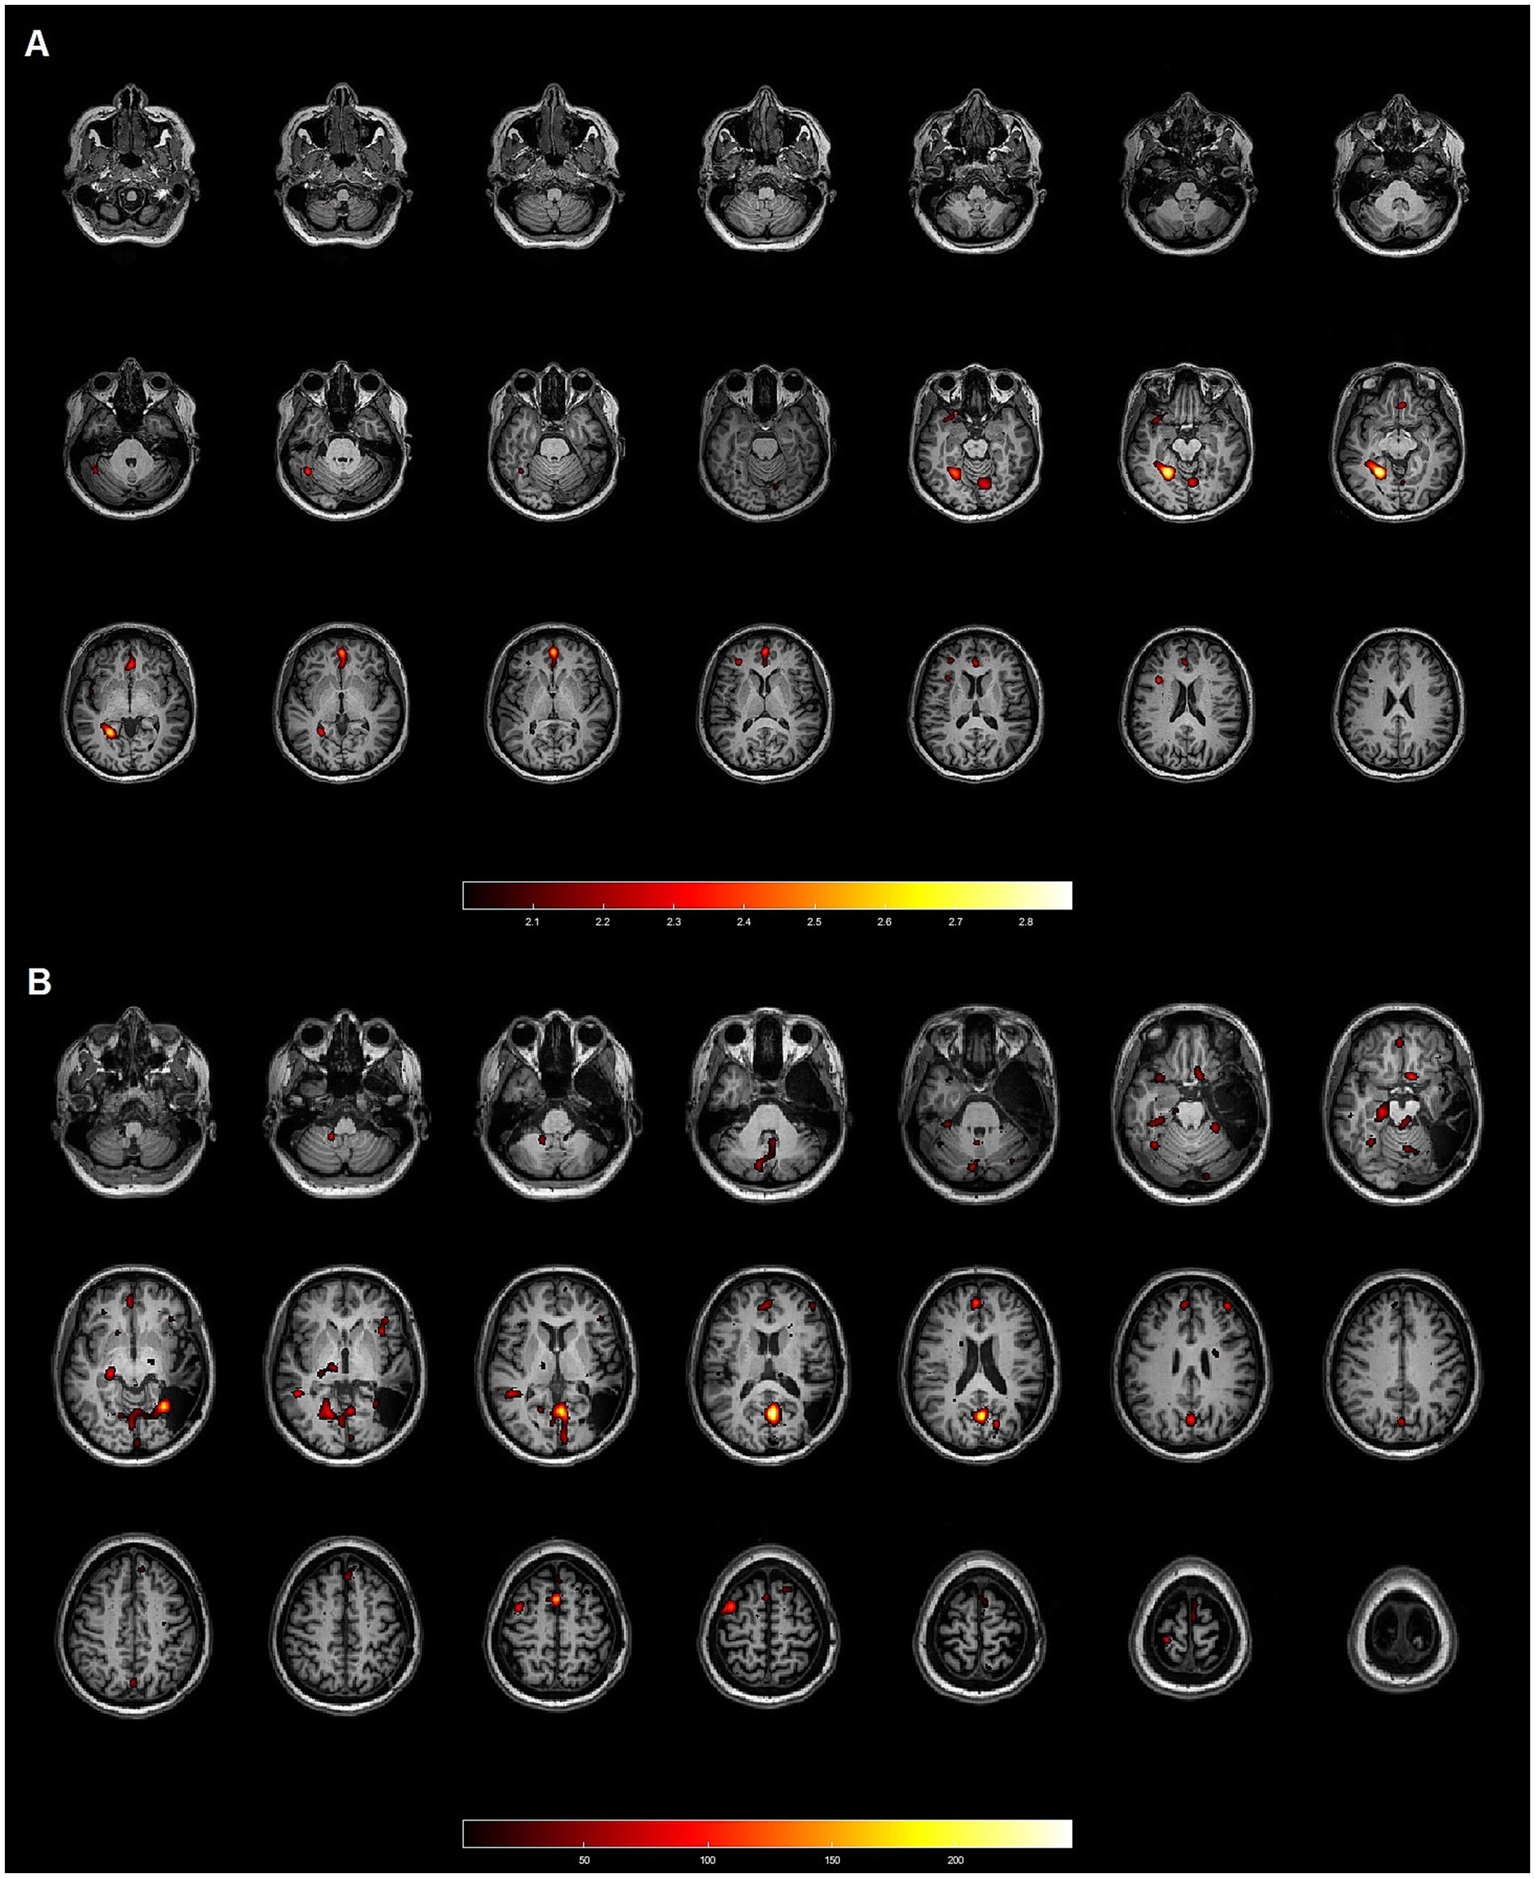

Figure 2

Patient 17: 45-year-old female with focal cortical dysplasia (FCD) IB in the right temporal lobe. Neither method demonstrated concordance with the gold standard. (A) Axial slices from the SISCOM analysis using SPM, showing multiple clusters discordant with the EZ, which was located in the right temporal lobe. (B) Axial slices from the Analyze software, also displaying multiple clusters inconsistent with the EZ in the right temporal lobe.